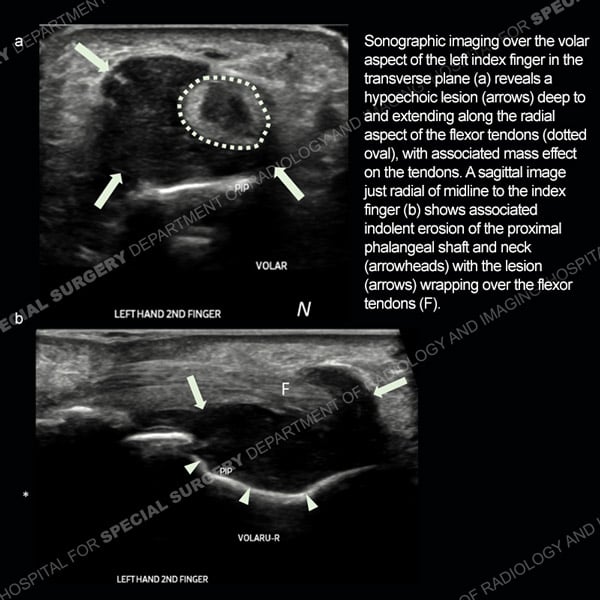

![]() |

Featured Ultrasound of the Month CaseCase 185: 55-year-old woman with right foot pain from naviculocuneiform joint osteoarthritis. |